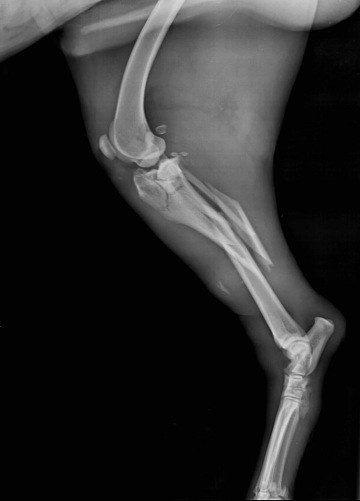

RTG vyšetření skeletu a kloubů